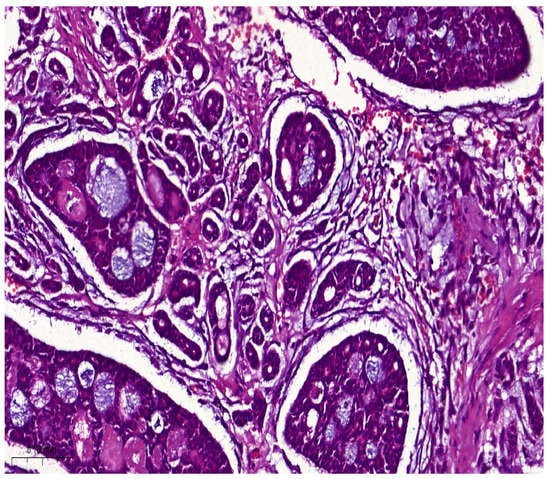

Histologically, salivary nonsolid AdCCs showed biphasic cell populations arranged in alternate cribriform and tubular architectures (Figure 1). The cribriform pattern demonstrated nests of neoplastic cells with hyperchromatic, angulated nuclei arranged in microcystic and macrocystic spaces. These pseudocystic cavities were occasionally filled with hyaline or basophilic mucoid material. The histologic features in the major salivary glands did not differ much from those in the minor salivary glands. However, solid nests of AdCC favored submucosal infiltration in the minor salivary glands (Figure 2, Case #15). Sinonasal AdCC revealed nests of cribriform and solid areas, while extensive hyalinization was recapitulating a jigsaw puzzle-like pattern (Figure 3). The cells of sinonasal AdCC were sometimes basaloid, with dark, hyperchromatic nuclei. The cells were typically arranged in a palisading pattern around the cystic spaces. A few salivary AdCCs revealed basaloid cells arranged in solid growth patterns that were insufficient for diagnosis as high-grade AdCCs. Mammary SB-AdCC revealed areas of cribriform, a solid growth pattern (>90%), and a basaloid appearance, with myxoid or hyalinized stroma. Ductules were present within the tumor islands. Small cysts and pseudoglandular structures were occasionally seen (Figure 4). This variant is characterized by the presence of small, basal-like cells with scant cytoplasm. The basaloid variant was associated with a higher risk of metastasis and a poorer prognosis. All neoplastic cells were positive for IHC SOX10, CK7, CD117, p63, and KI67. The clinical and molecular findings are shown in Table 1. There, all of the AdCC cases had MYB rearrangements detected by fluorescence in situ hybridization (FISH), which is a common genetic alteration observed in AdCC. Specifically, MYB was found to be fused with NFIB and/or KMT2C/KMT2D in AdCC cases from sinonasal and minor SG sites. MYB::NFIB fusion is a well-known molecular alteration that occurs in approximately 30–70% of AdCC cases and has been associated with better prognosis compared to cases without this fusion. On the other hand, MYB::KMT2C/D fusions were less common but have also been reported in cases from salivary and sinonasal AdCCs. Although this is the first study to report this finding, its clinical significance is yet to be fully elucidated. In addition to FISH, some AdCC cases were also analyzed using next-generation sequencing. In Table 1, NGS was performed in several AdCC cases from sinonasal, minor SG, and parotid gland sites. MYB::NFIB and MYB::KMT2D fusions were detected in these cases, which is consistent with the FISH results. Notably, some cases were not analyzable by NGS, which may be due to various reasons such as low DNA quality or quantity. The median score for Group 1 was 70 (IQR: 60–80), the median score for Group 2 was 85 (IQR: 75–90), and the median score for Group 3 was 60 (IQR: 55–70). The results indicate that there was a significant difference between Group 1 and Group 3 (p < 0.05) and between Group 2 and Group 3 (p < 0.05) but not between Group 1 and Group 2 (p > 0.05). This suggests that the solid mammary AdCCs with basaloid features (Group 3) have different characteristics compared to the other two groups.

Figure 4.

Mammary SB-AdCC revealed areas of cribriform, a solid growth pattern (>90%), and a basaloid appearance, with myxoid or hyalinized stroma. Ductules were present within the tumor islands (H&E stain; magnification ×5).